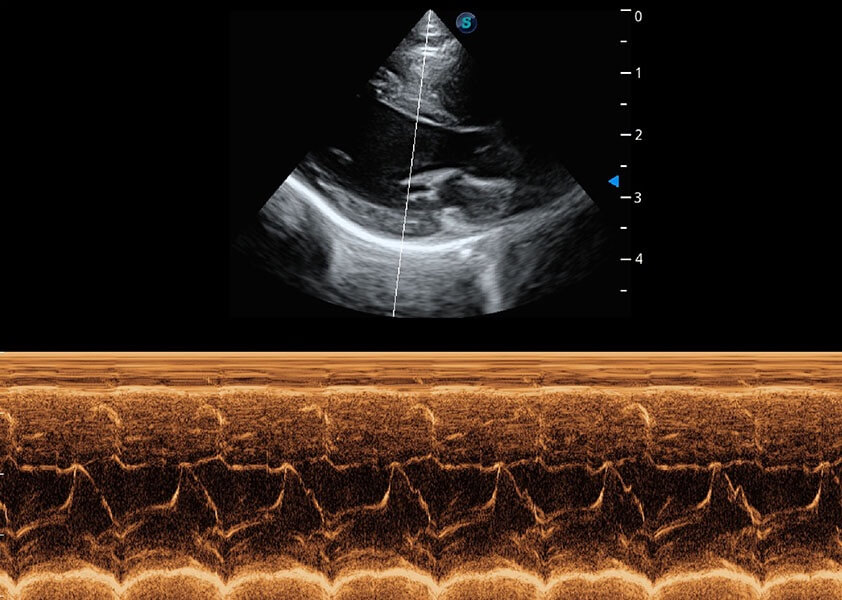

• AMM 解剖M型

通过360度任意调节3条M型取样线,在同一心动周期上观察心脏不同位置的运动曲线,得到准确的心功能测量数据,有效评估心肌运动及左心室功能。

(犬)心脏组织多普勒

(犬)乳头肌短轴

(猫)二尖瓣M型